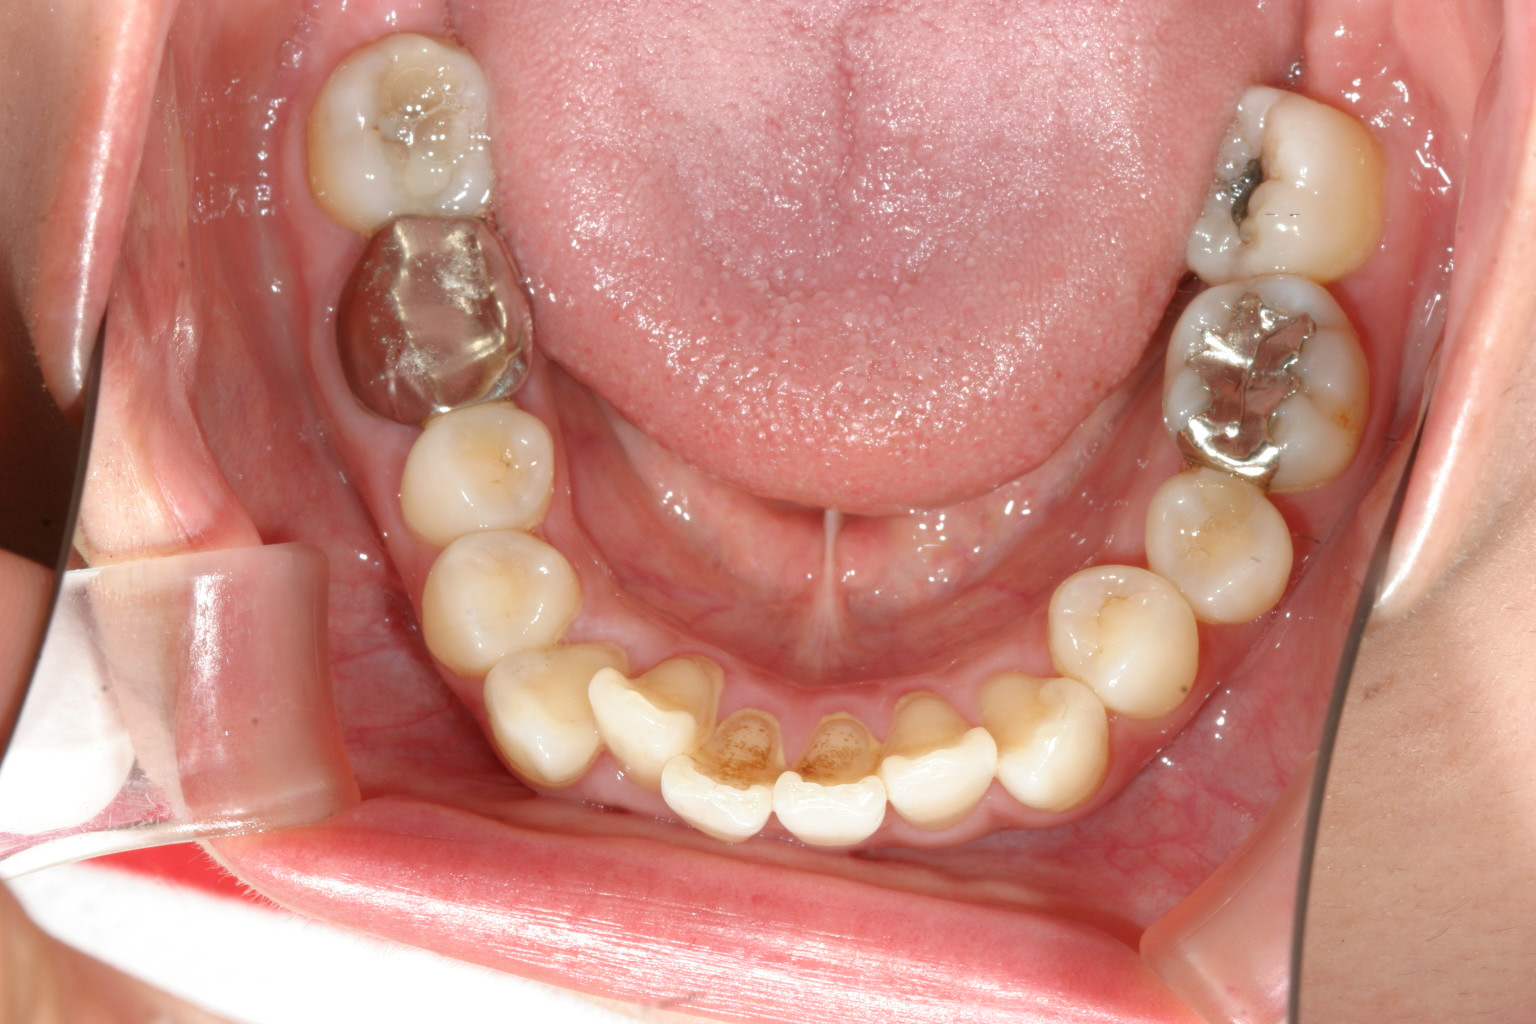

下顎のアーチは綺麗に並びました。

臼歯部離開の為前歯に自家製咬合閉鎖ジグを前歯に咬まして臼歯部にボタン付けてアップダウンエラスティック使用。

あとは上顎の歯のねじれ改善、下顎の舌側転移も難なく出っ歯も改善しました。